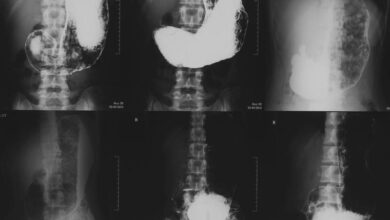

Рентген суставов для выявления артрита

Рентген диагностика Рентген суставов является одним из основных методов визуализации для выявления артрита. Этот метод позволяет врачам получить детальные изображения…